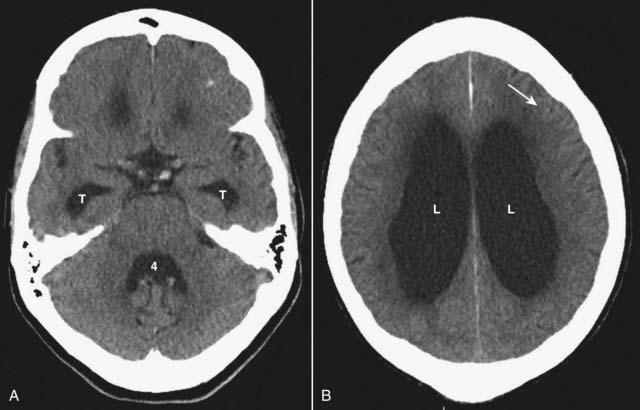

image In hydrocephalus, the ventricles are usually disproportionately dilated compared to the sulci, whereas both the ventricles and sulci are proportionately enlarged in cerebral atrophy.

image The temporal horns are particularly sensitive to increases in CSF pressure. In the absence of hydrocephalus, the temporal horns are barely visible. With hydrocephalus the temporal horns may be greater than 2 mm in size (Fig. 25-22).

image

Figure 25-22 Noncommunicating hydrocephalus.

A, There is dilatation of the temporal horns (solid white arrows) and the 4th ventricle is compressed and nearly invisible (dotted white arrow). A hemorrhagic metastatic lesion (solid black arrow) is present that is obstructing the 4th ventricle. B, The frontal horns of the lateral ventricles (L) and 3rd ventricle (3) are dilated, but note that the sulci are not dilated. This form of hydrocephalus is the result of obstruction to the outflow of cerebrospinal fluid from the ventricles.

image Obstructive hydrocephalus is divided into two major categories: communicating (extraventricular obstruction) and noncommunicating (intraventricular obstruction).

image Communicating hydrocephalus is due to abnormalities that inhibit the resorption of cerebrospinal fluid, most often at the level of the arachnoid villi (Fig. 25-23).

CSF flow through the ventricles and over the convexities normally occurs unimpeded. Reabsorption through the arachnoid villi can become restricted by such things as subarachnoid hemorrhage or meningitis.

Figure 25-23 Communicating hydrocephalus.

Communicating hydrocephalus is due to abnormalities that inhibit the resorption of cerebrospinal fluid, most often at the level of the arachnoid villi. A, Classically, the 4th ventricle is dilated in communicating hydrocephalus (4) but normal in size in noncommunicating hydrocephalus. The temporal horns (T) are particularly sensitive to increases in intraventricular volume or pressure and are dilated in this patient. B, The frontal horns (F), occipital horns (O), and 3rd ventricle (3) are markedly dilated. There is a disproportionate dilatation of the ventricles compared to the sulci (which are normal to small in this case). Communicating hydrocephalus is usually treated with a ventricular shunt.

imageClassically, the 4th ventricle is dilated in communicating hydrocephalus and normal in size in noncommunicating hydrocephalus.

Communicating hydrocephalus is usually treated with a ventricular shunt.